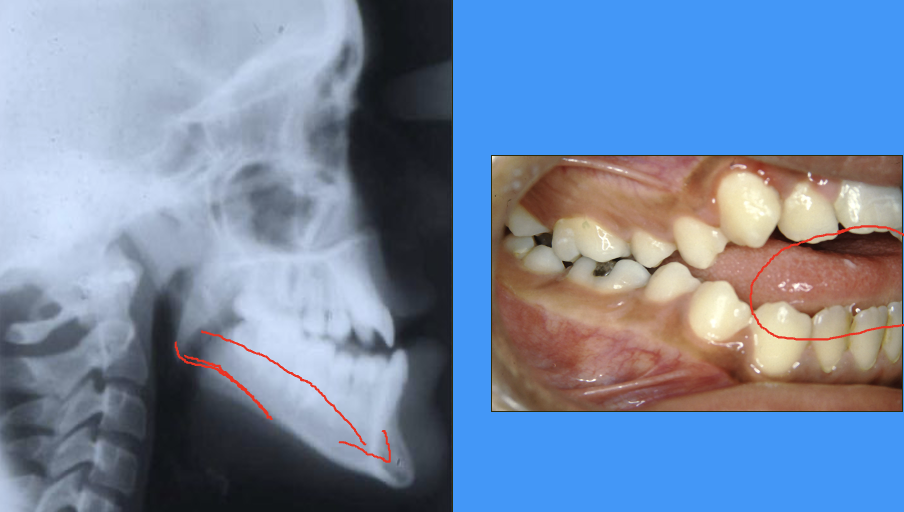

radiograph and clinical image showing psoterior growth rotation of mandible

(not same radiograph and clinical image)

Björk’s findings pt. 2

minority had a ‘posterior’ rotation

mandibular plane angle increases » anterior open bite

more skeletal class II occlusion

leads to late lower incisor crowding?

genetic link?